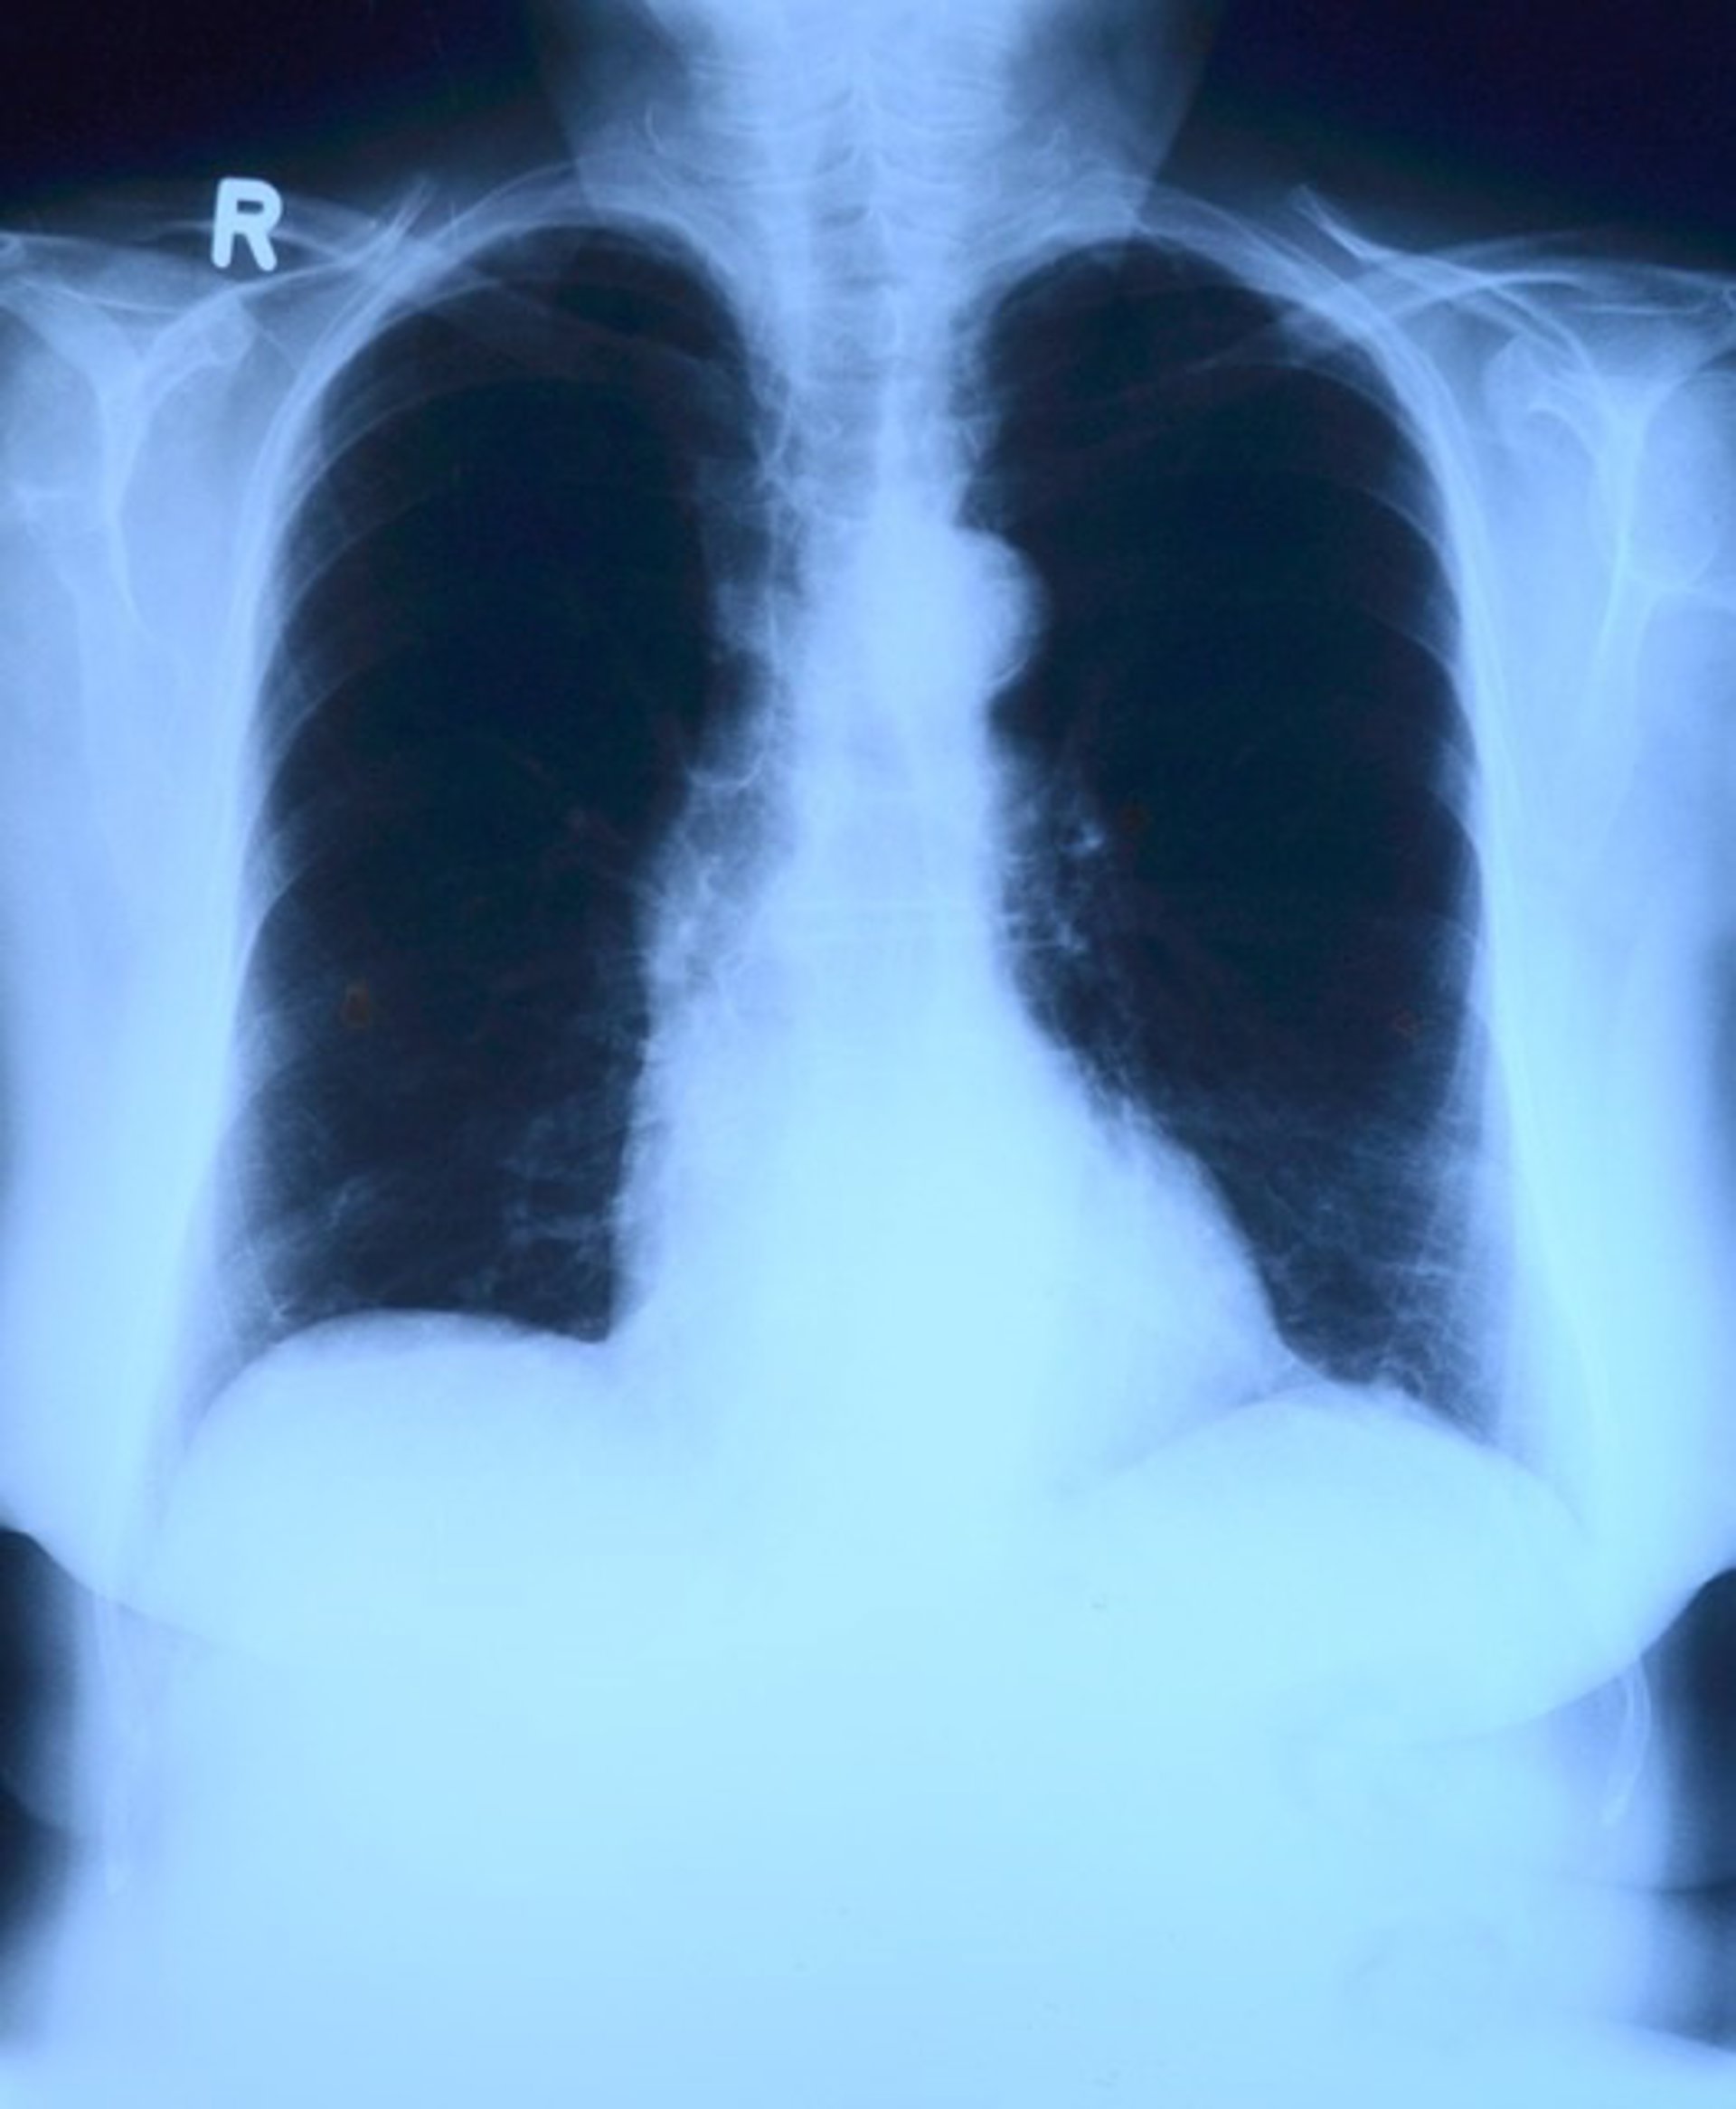

Pulmones, radiografía

PIXABAY - Archivo